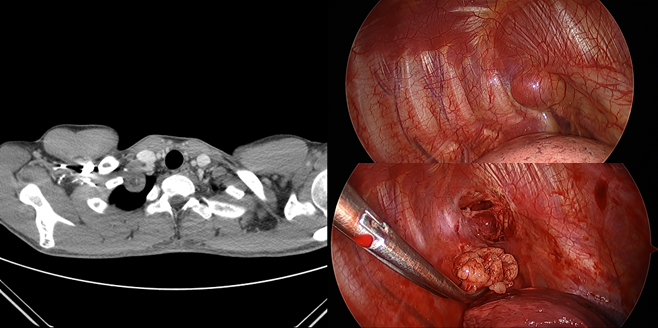

Methods : At October 2015 and January 2017, 2 patients underwent enucleation of neurilemmoma at the thoracic apex using a thoracoscopy with three small holes in the chest.

Results : The neurilemmoma was enucleated meticulously by freer and endoscissors. The patients have lived without any complications and recurrence so far. First patient’s operation time was 1 hour 52 minutes and estimated blood loss was scanty and chest tube was removed at post-operative day 2 and the patient was discharged at post-operative day 3. Second patient’s operation time was 1 hour 37 minutes and estimated blood loss was scanty and chest tube was removed at post-operative day 1 and the patient was discharged at post-operative day 2.

Conclusion : Thoracoscopic enucleation of neurilemmoma can provide alternative way to remove the neurilemmoma at the thoracic apex less invasively comparing with conventional posterolateral thoracotomy or supraclavicular incision. This method has advantages in aspects of pain, scar and shortened hospital-day without complications.